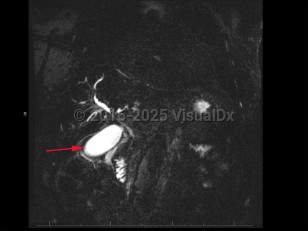

Cholangiocarcinoma refers to biliary tree malignancies, primarily adenocarcinomas, of epithelial cell origin. They are typically categorized as intrahepatic, perihilar, or distal.

Patients with cholangiocarcinoma will often have elevations in their liver function tests (total and direct bilirubin) and liver enzymes (aspartate transaminase [AST], alanine transaminase [ALT], alkaline phosphatase), although these are nonspecific findings. Elevations in cancer antigen (CA) 19-9, a tumor marker, can be suggestive of cholangiocarcinoma but are limited by nonspecificity. Diagnosis typically requires tissue sampling via endoscopic retrograde cholangiopancreatography (ERCP) with brushing.

Fibroblast growth factor receptor (FGFR) plays a role in driving the disease, and inhibitors of that growth factor are under study.